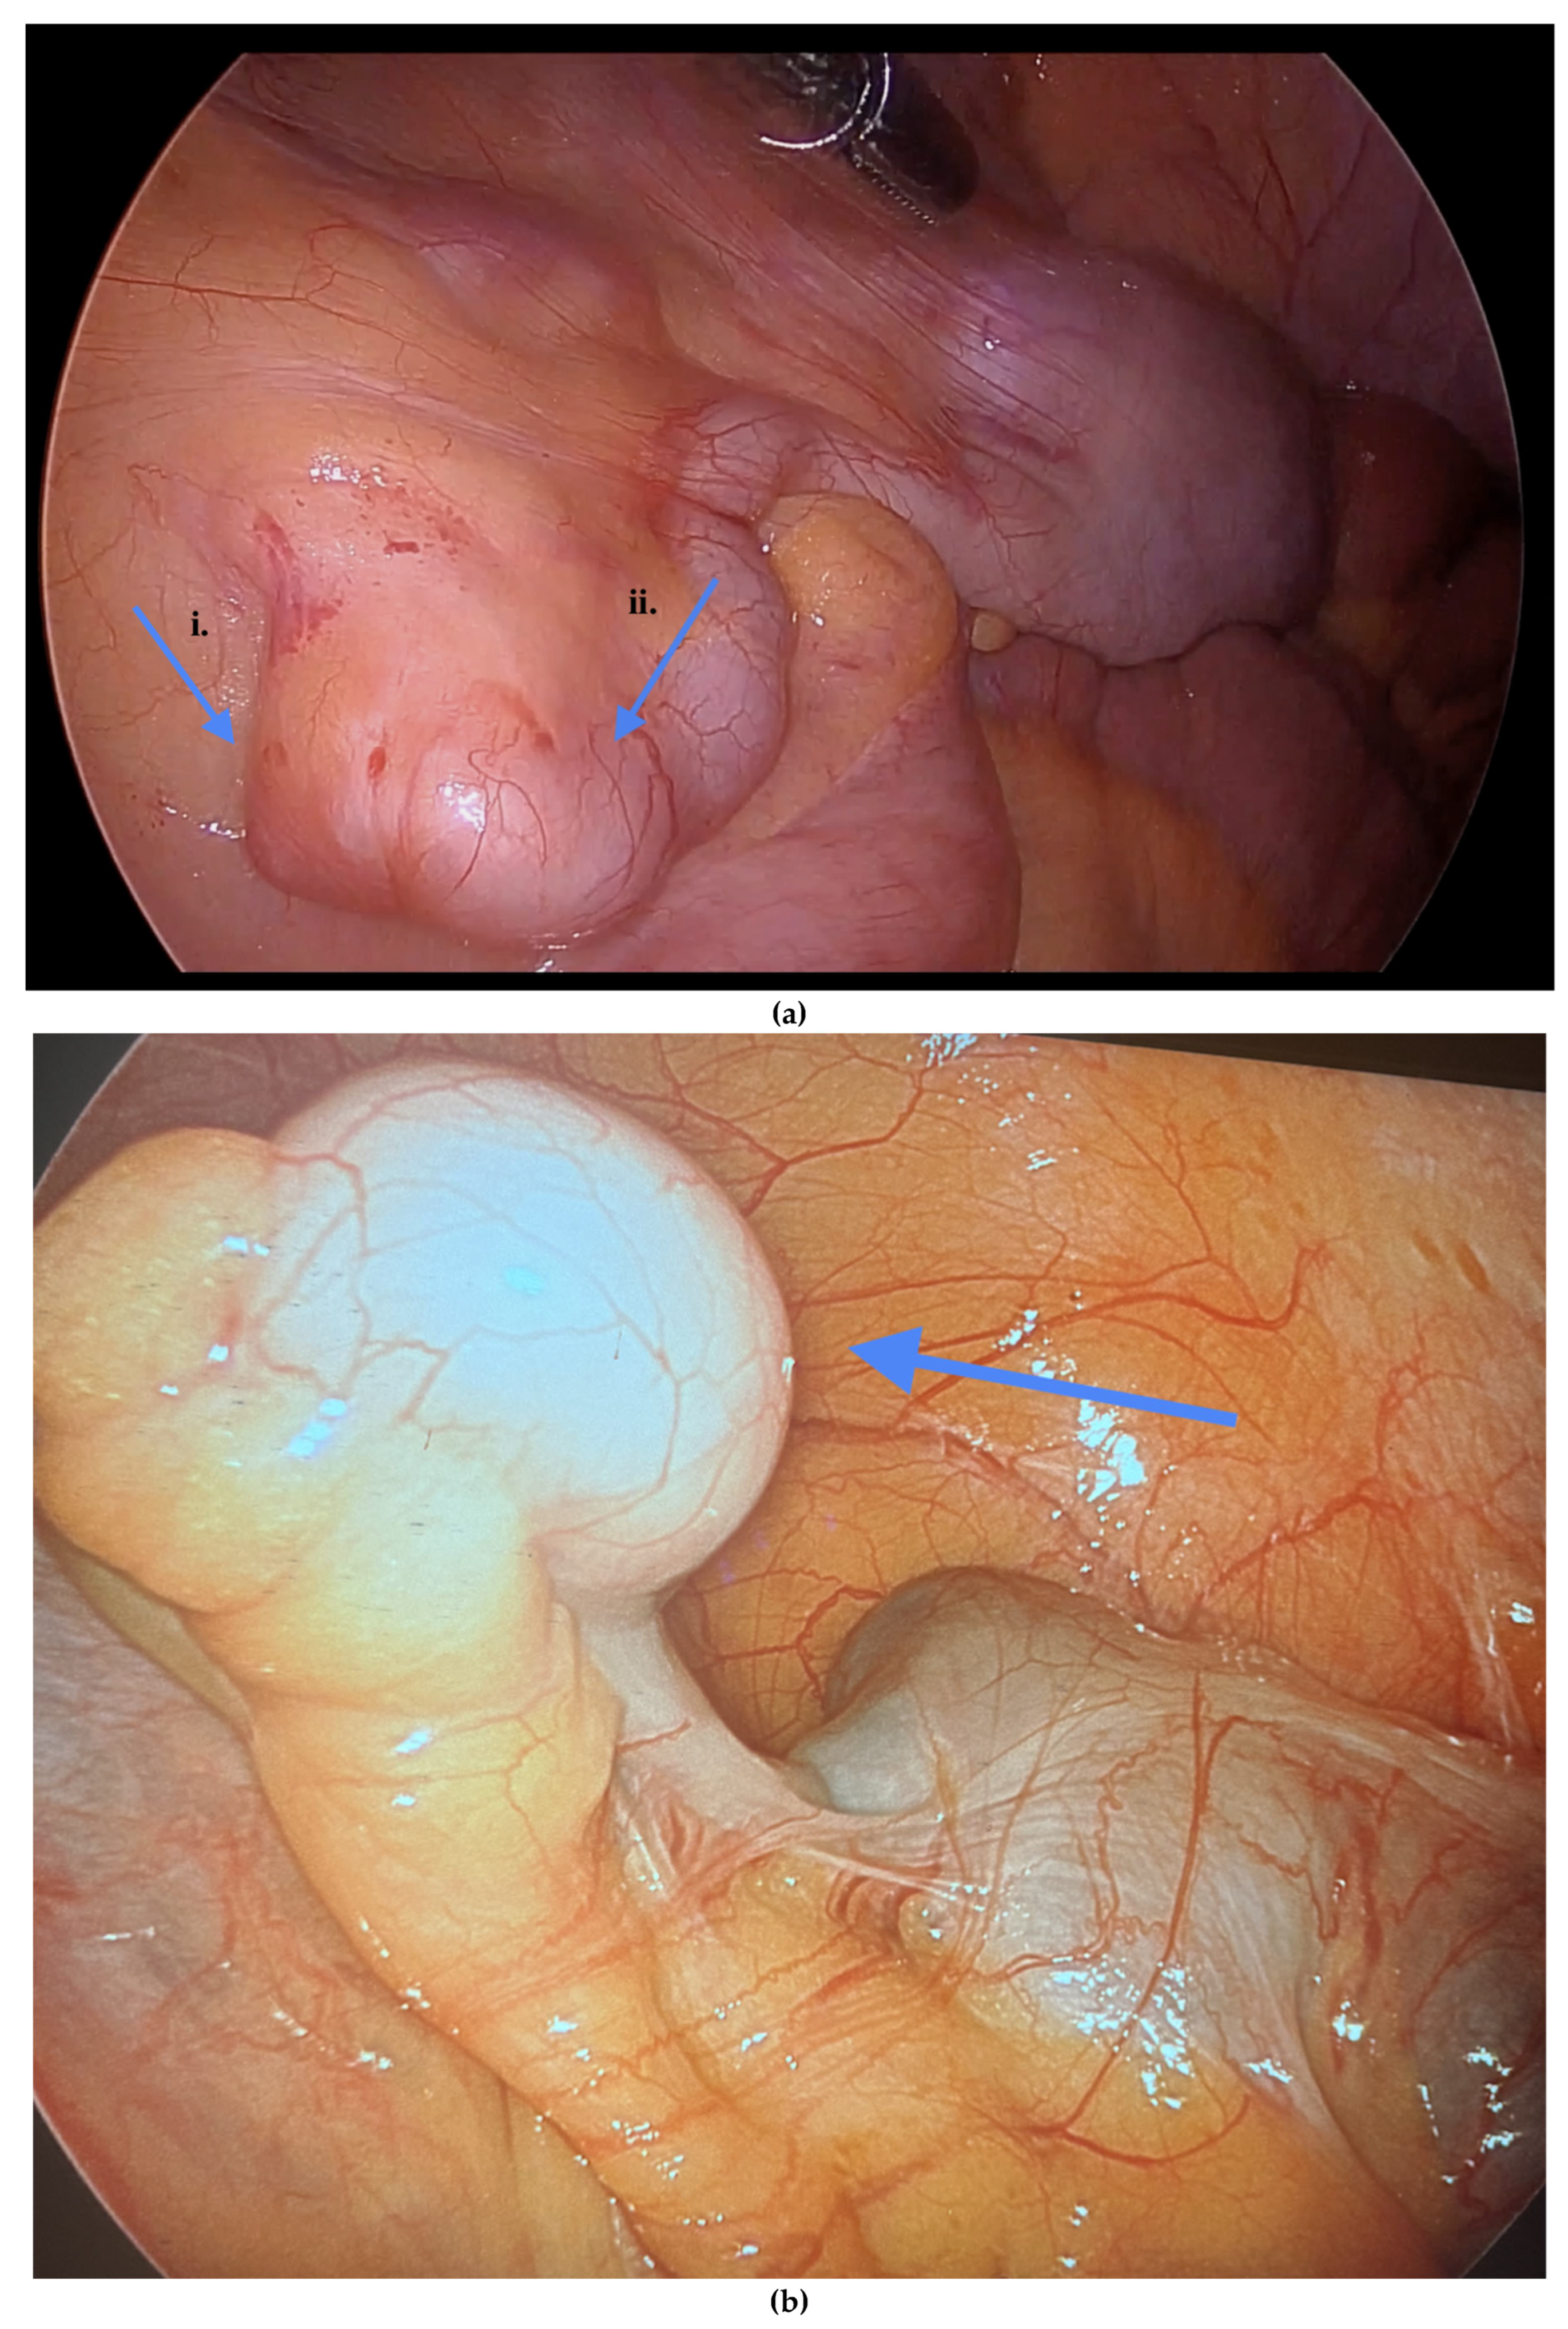

Informed consent was obtained preoperatively, which included a discussion of the possibility of intraoperative appendectomy if appendiceal abnormalities were identified. During surgery, after optimal excision and ablation of endometriotic lesions, the appendix was carefully evaluated for evidence of endometriotic implants, serosal abnormalities, adhesions, fibrous obliteration, or features suggestive of acute or chronic appendicitis (Figure 1, Figure 2 and Figure 3). If abnormal findings were present, intravenous metronidazole was administered for infection prophylaxis, and a laparoscopic appendectomy was performed using the existing port sites [15]. The surgical technique included division of the mesoappendix, followed by transection and closure of the appendiceal base using a vascular stapler. The specimen was placed into a laparoscopic retrieval pouch and sent for histopathologic analysis [15,16].

Among the 216 patients with confirmed appendiceal abnormalities, many presented with more than one pathological finding (Figure 1, Figure 2 and Figure 3). Specifically, 34 patients (14.41%) had histologically confirmed appendiceal endometriosis lesions, 140 patients (59.32%) showed focal or serosal adhesions, 82 (34.75%) demonstrated fibrous obliteration, typically observed as obliteration of the appendiceal tip, and 20 (8.47%) exhibited signs of inflammation. Notably, three cases were diagnosed with neuroendocrine tumors of the appendix: one was confirmed to be malignant, while the other two were benign (Table 2).

Figure 1. (a) Endometriosis on the appendix and mesoappendix. (b) Endometriosis nodule at the base of the appendix. Blue arrows indicate (a) endometriosis involving the appendix and mesoappendix, and (b) an endometriosis nodule at the base of the appendix.

Figure 2. (a) i. Dense adhesions of the appendix to the uterus. ii. Endometriosis surrounding the peri appendix. (b) Vesicular lesions on the appendix. Blue arrows indicate (a) dense adhesions of the appendix to the uterus with endometriosis surrounding the peri-appendix, and (b) vesicular lesions on the appendix.